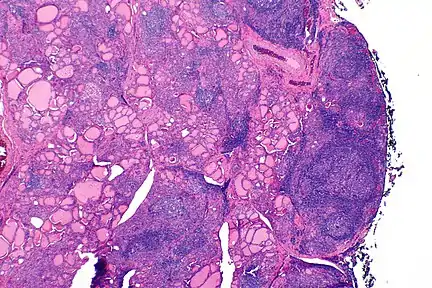

| The thyroid of someone with Hashimoto's thyroiditis as seen with a microscope at low magnification | |

Gross morphological changes within the thyroid are seen in the general enlargement, which is far more locally nodular and irregular than more diffuse patterns (such as that of hyperthyroidism). While the capsule is intact and the gland itself is still distinct from surrounding tissue, microscopic examination can provide a more revealing indication of the level of damage.[24]

Histologically, the hypersensitivity is seen as diffuse parenchymal infiltration by lymphocytes, particularly plasma B-cells, which can often be seen as secondary lymphoid follicles (germinal centers, not to be confused with the normally present colloid-filled follicles that constitute the thyroid). Atrophy of the colloid bodies is lined by Hürthle cells, cells with intensely eosinophilic, granular cytoplasm, a metaplasia from the normal cuboidal cells that constitute the lining of the thyroid follicles. Severe thyroid atrophy presents often with denser fibrotic bands of collagen that remains within the confines of the thyroid capsule.[25]